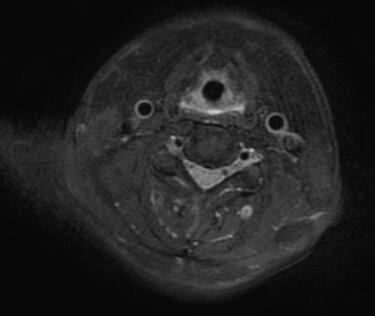

马德龙病的影像表现为颈项部等处脂肪组织蓄积增厚,可累及皮下或肌肉间隙,脂肪蓄积处没有包膜形成,蓄积脂肪内可有线状或网状纤维间隔,病变常常左右对称,颈部肌肉可受压、变细,蓄积脂肪组织内可有钙化或骨化。

李某颈部MRI